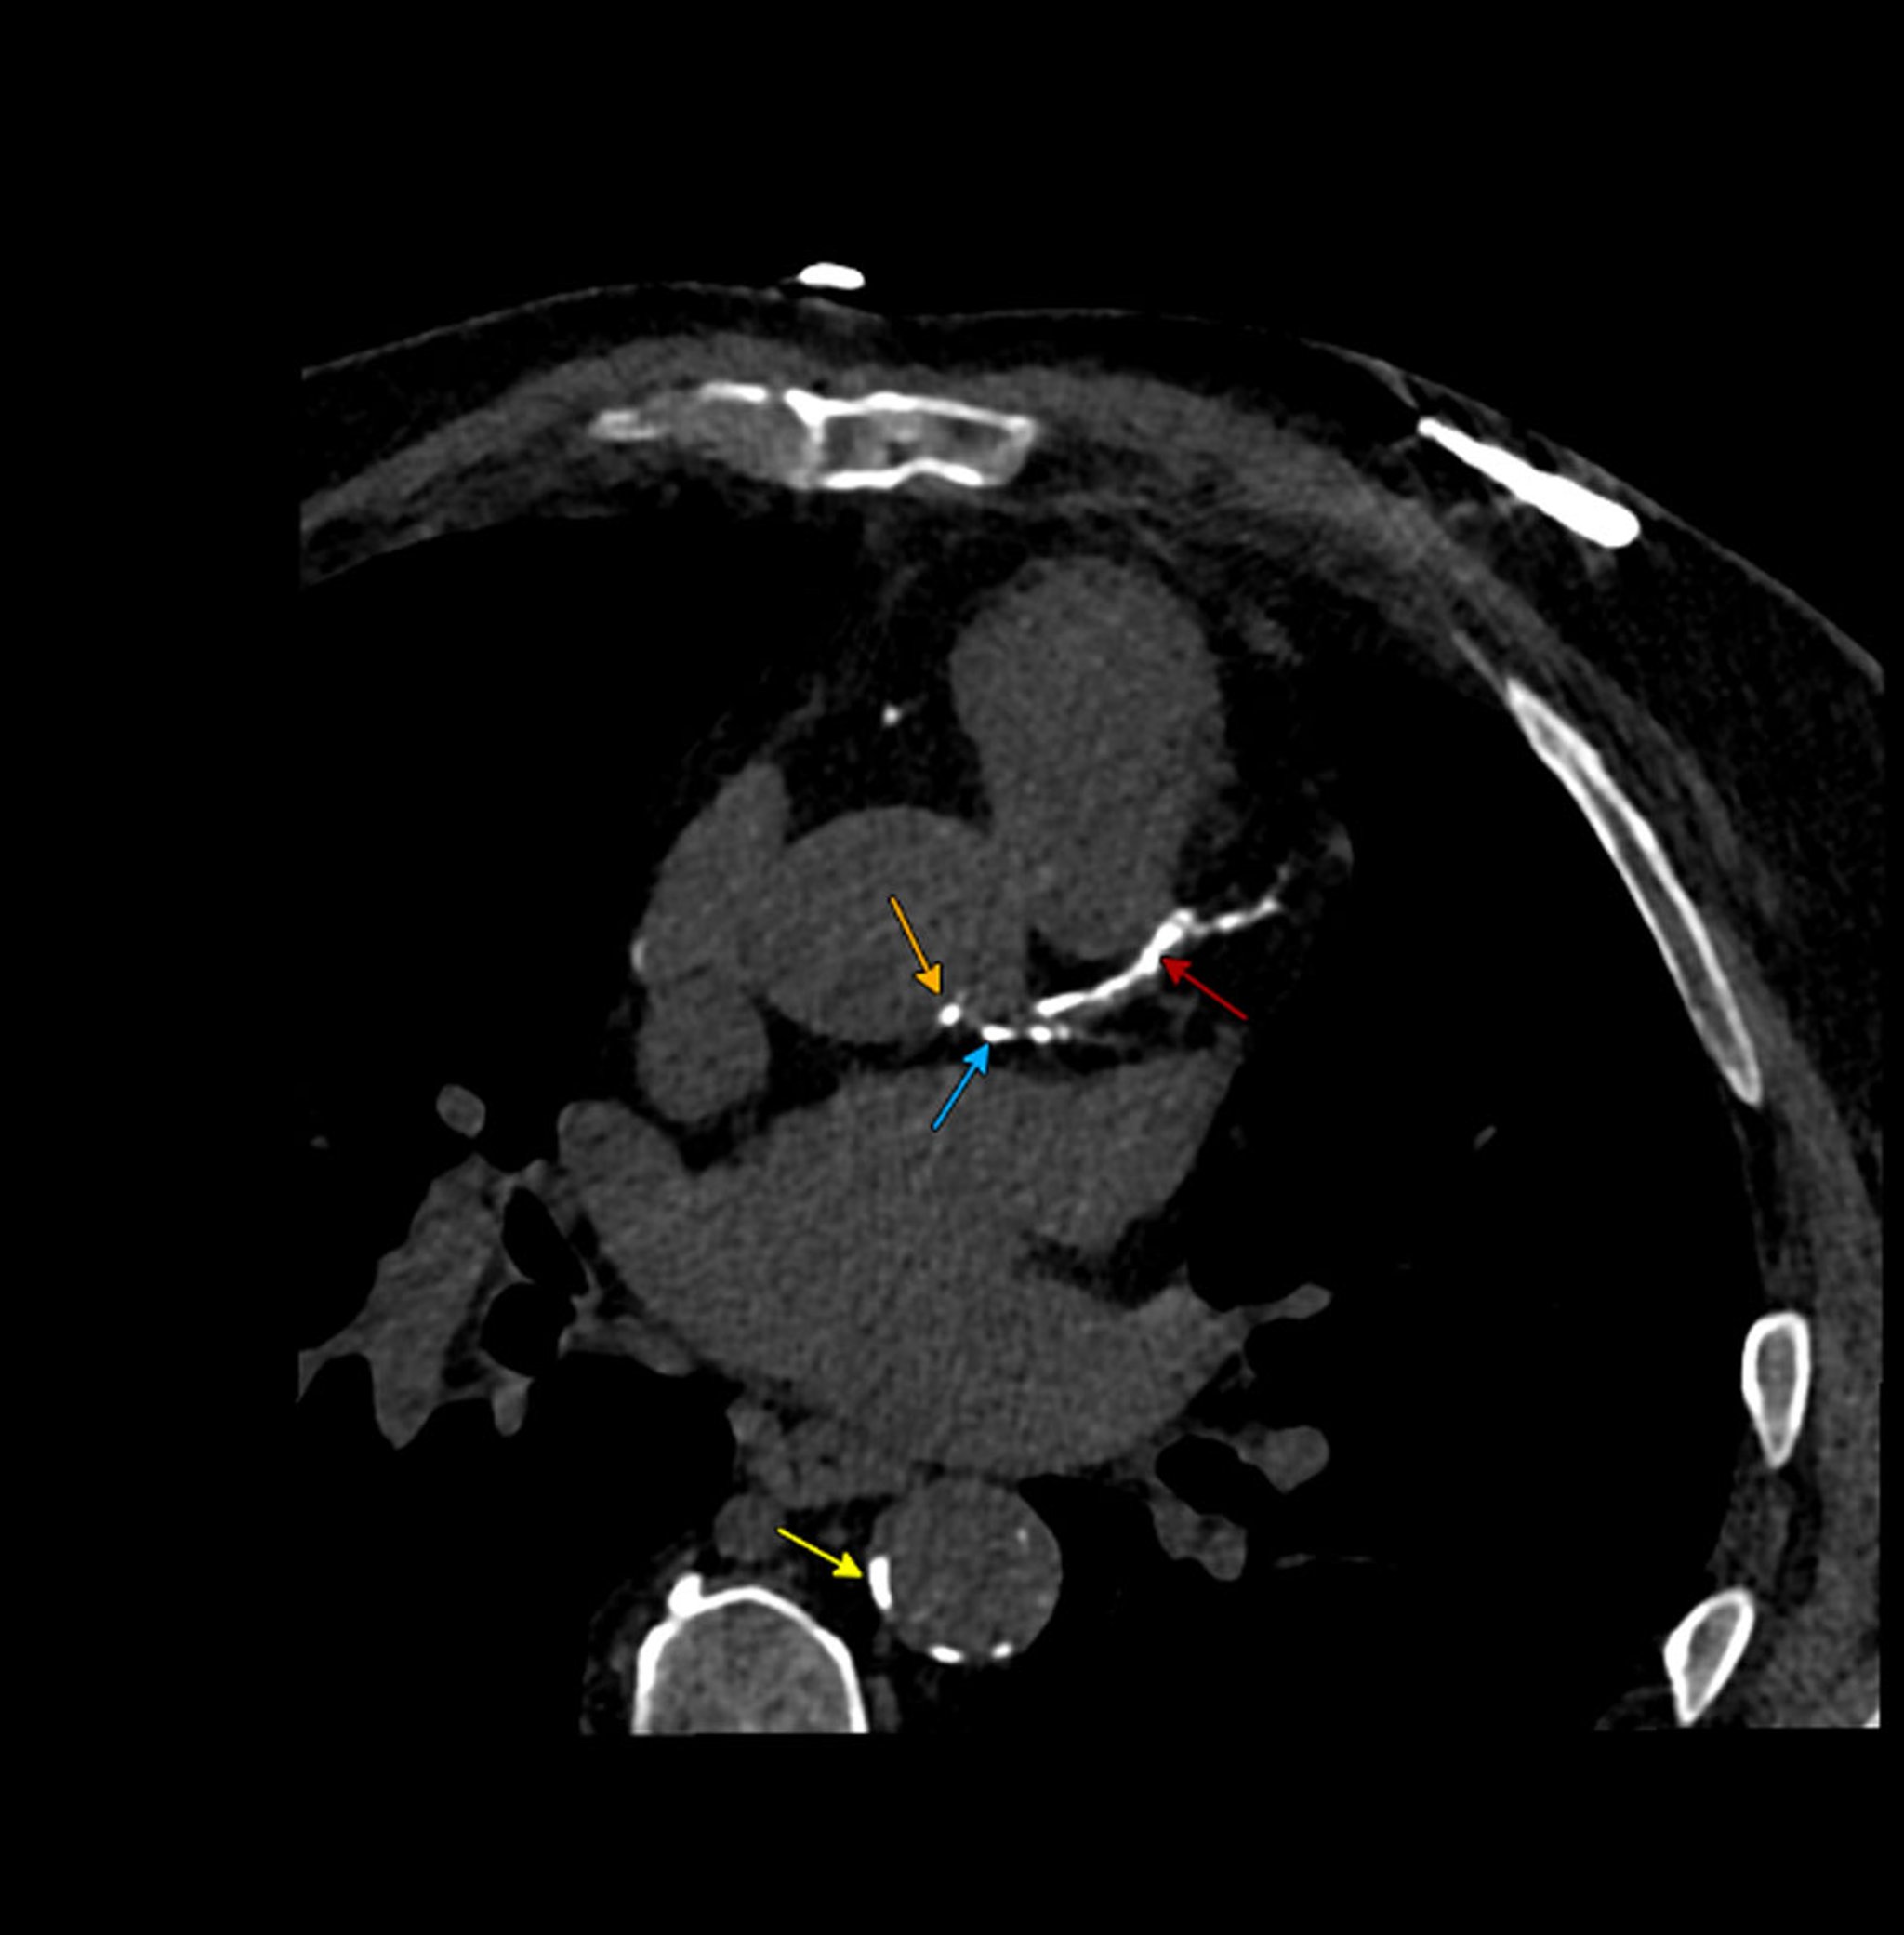

• CT angiography (CTA): CTA uses iodinated contrast-enhanced CT to evaluate atherosclerotic plaque morphology and detect stenosis severity with high spatial resolution. This technique involves ionizing radiation and can be applied to any vascular bed, making it ideal for small, mobile vascular beds like the coronary arteries.

• CT fractional flow reserve (FFR): This technique combines CTA with computational fluid dynamics to assess the physiologic significance of coronary artery stenoses by estimating the pressure drop across a coronary lesion.

• Positron emission tomography (PET) molecular imaging: This technique uses molecular imaging tracers to detect metabolic activity of atherosclerotic plaques (F18-fluorodeoxyglucose [FDG]) or microcalcifications (F18-sodium fluoride).: This technique uses molecular imaging tracers to detect metabolic activity of atherosclerotic plaques (F18-fluorodeoxyglucose [FDG]) or microcalcifications (F18-sodium fluoride).

• Fractional flow reserve (FFR): A pressure wire is used to evaluate the hemodynamic significance of a stenosis. FFR is based on the ratio of pressure distal and proximal to a stenosis in the presence of maximal blood flow (hyperemia, typically induced by adenosine). In coronary arteries, an FFR ≤ 0.80 indicates a hemodynamically significant stenosis.